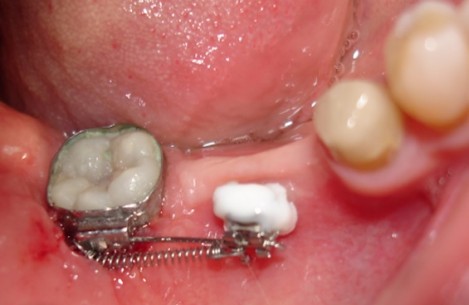

Problems in the treatment of ankylosing deciduous molars

Анкилозата на зъб се определя като анатомично сливане на алвеоларна кост с цимента на зъбния корен.Този феномен може да се появи по време на пробив на зъба или след това.